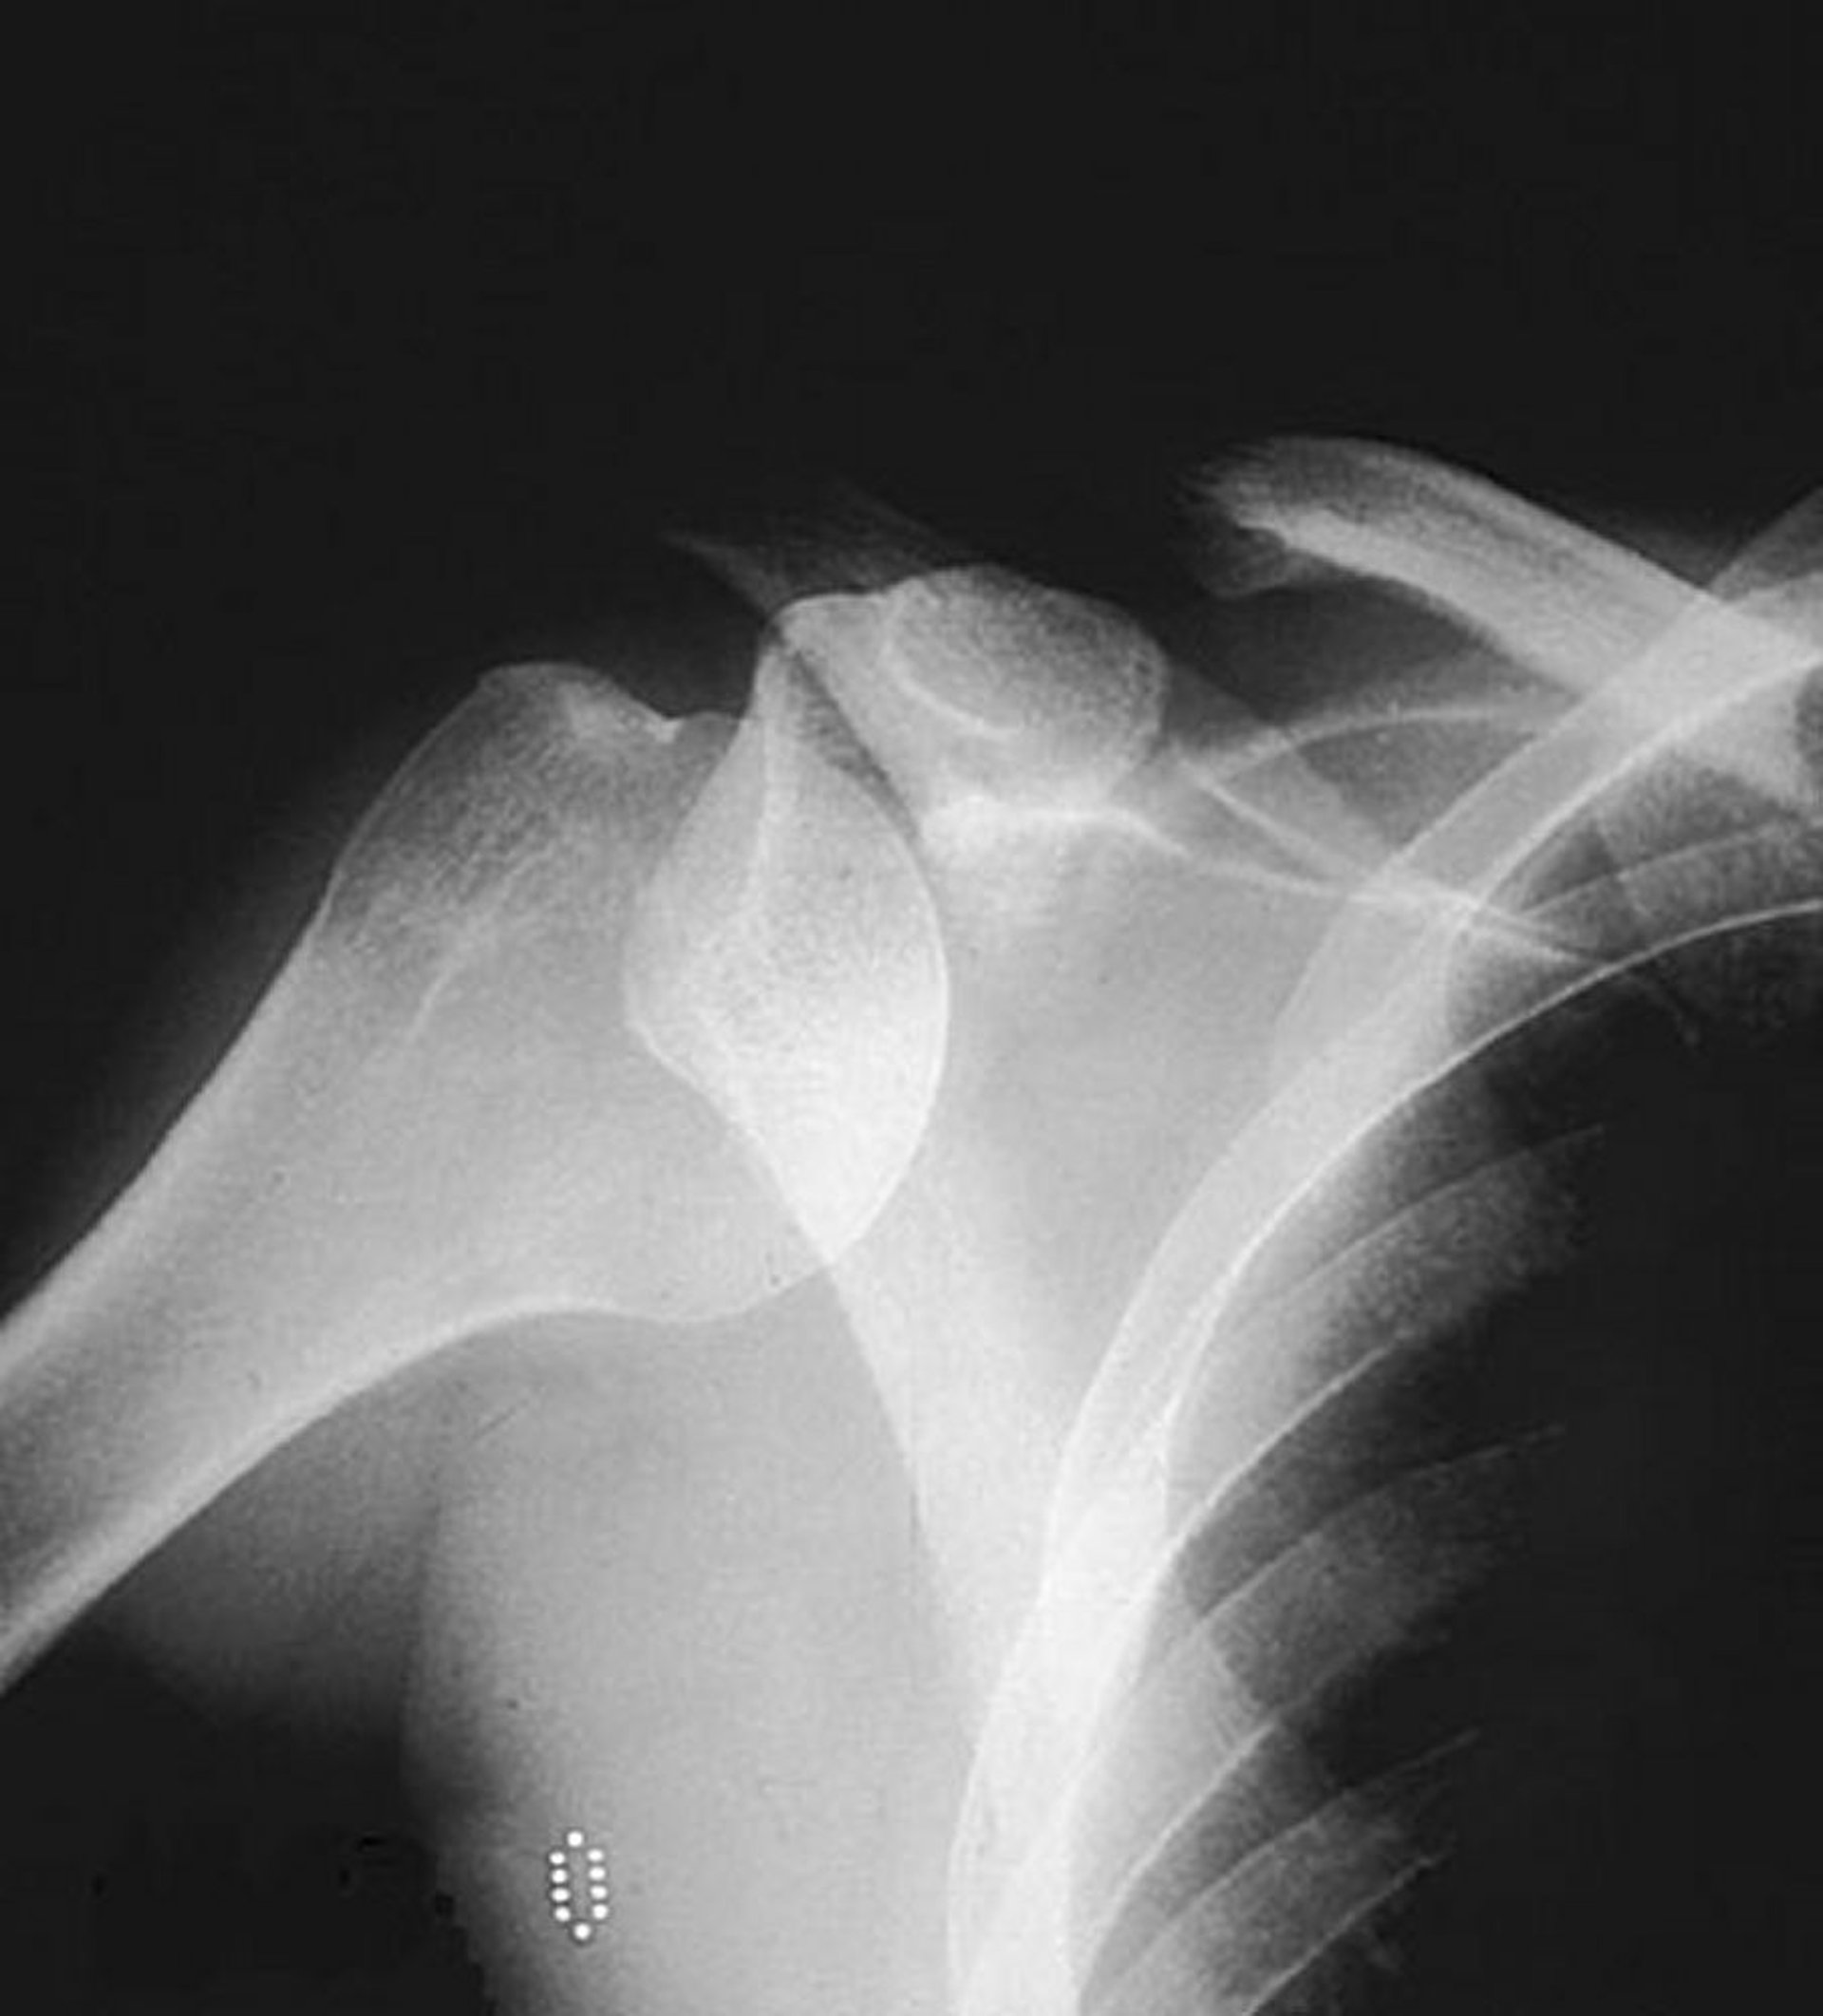

Lussazione gleno-omerale anteriore (spalla)

Una radiografia antero-posteriore normale mostra la testa omerale fuori dalla sua posizione abituale all'interno della fossa glenoidea, suggerendo una lussazione anteriore.